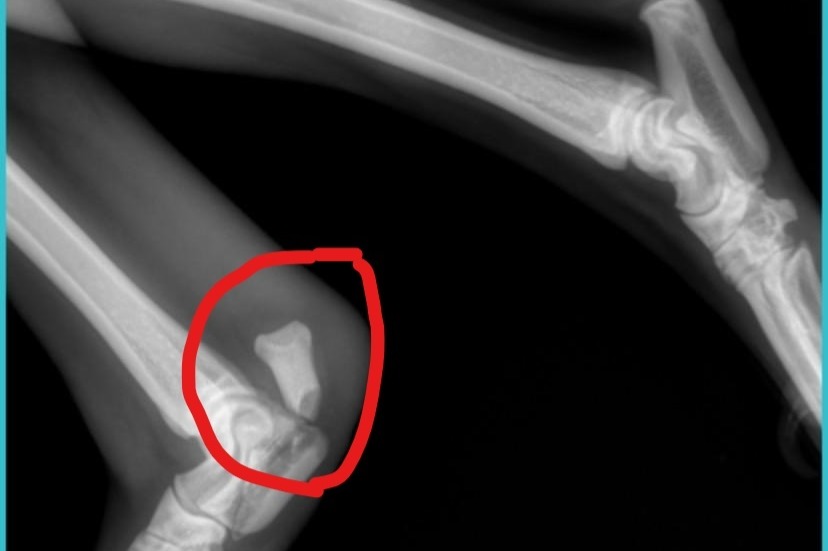

Sometimes puppies have a mind of their own....and sweet Alice proved that on Wednesday, Feb 17th when she jumped out of a moving vehicle (25 mph) attempting to make new doggie friends.  Unfortunately, this has led to puppy Alice needing surgery on her right, rear leg or the leg will need to be amputated.  The injury is called a Calcanean Avulsion Fracture and can be seen in the photo.  Surgery will happen Saturday the 27th with your aid; the vet says immediate help is the best option.  Alice is currently awaiting surgery with meds for pain/rest and her leg wrapped.  Aarin has already paid $550 for this diagnosis and needs $4,000 more for surgery, splints, and wraps.